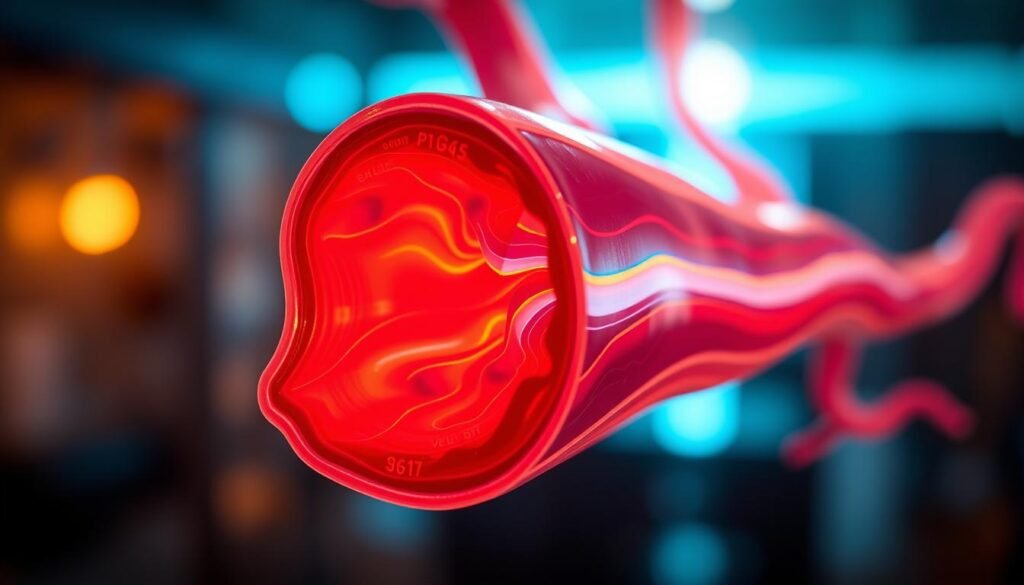

Qu’est-ce qu’un doppler veineux ? Définition et Utilisation

Doppler veineux : définition, utilisation et importance dans le diagnostic des troubles veineux. Informations complètes pour comprendre cet examen.